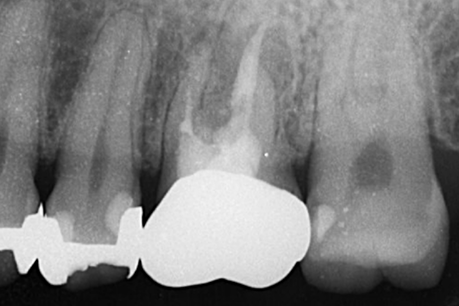

左上6番目

治療の内容:パーフォレーションにより根分岐部病変があり、根尖病変もある症例。歯内歯周病変で歯周病と根尖病変が合併している難治症例。根管治療後分岐部病変が治らなかったため遠心頬側根の歯根切除を行いその後近心頬側根が石灰化しておりそこの根尖病変も治癒が悪かったため歯根端切除も行った。歯周ポケットがなくなり、根尖病変も治癒傾向なため補綴処置を行なった。

治療の期間:8か月

回数:根管治療4回、コア1回、歯根切除1回、抜糸1回、歯根端切除1回、抜糸1回

金額:保険治療

治療のリスク・副作用:術後に歯根破折を起こしたり、清掃不良から歯周病や虫歯を作ることがある。